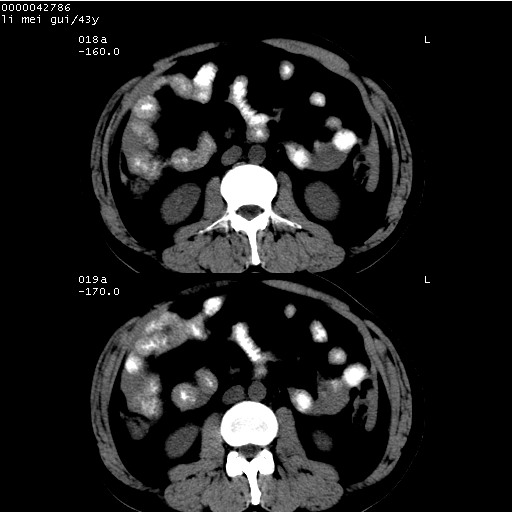

| 患者,男,43岁。突发腹痛2小时,面色苍白,难以平卧。自述近期无明确外伤史,为摩托车驾驶员。 腹部b超检查:脾脏中上极回声异常,肿瘤待排。 临床诊断:腹痛原因待查。 上中腹部ct轴位平扫+增强扫描(层厚10mm,螺距1.0,重建间隔10mm),图像如下: ![]() ![]() ![]() ![]() ![]() ![]() ![]() ![]() ![]() ![]() ![]() ![]() ![]() ![]() ![]() ![]() ![]() ![]() ![]() ![]() ![]() ![]() ![]() ![]() ![]() ![]() ![]() ![]() ![]() ![]() ![]() ![]() ![]() ![]() ![]() zrs发言:支持脾破裂 wwp发言:支持脾破裂并腹水。 xulianj发言:脾脏肿瘤破裂可能性大 zsl6918发言:不像肿瘤出血,考虑还是与外伤后引起的慢性出血有关 zzyy发言:平扫见肝周及脾周积液,脾内密度不均。脾内肿瘤较少见。还是外伤性脾破裂。 沈丘东方医院发言:脾门区一个不均匀强化病灶与其周液体相连多考虑脾占位破裂出血 yixianman001011发言:脾破裂并腹水是可以肯定的,具体原因多以肿瘤性破裂出血,脾脏淋巴瘤可能性大. 结果: 术后,经详细询问患者,其仔细回忆:一月前骑摩托时左侧腰部与别人有“轻微”触碰,因责任在自已,当时又无明显不适,未引起注意。 临床术后诊断:脾破裂并失血性休克(1.外伤性迟发性脾破裂。2.脾脏肿瘤破裂?) 术后标本病检:脾破裂并出血,未见明显肿瘤成份。 原贴地址:http://www.radinet.com.cn/forum_view.asp?forum_id=4&view_id=34070 |